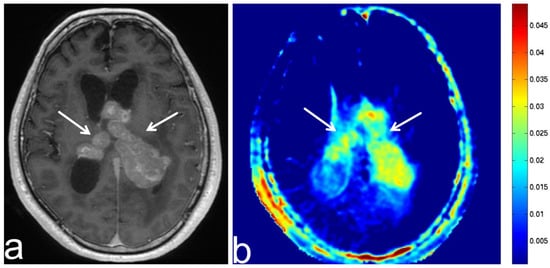

5.4. Malignant Lymphoma